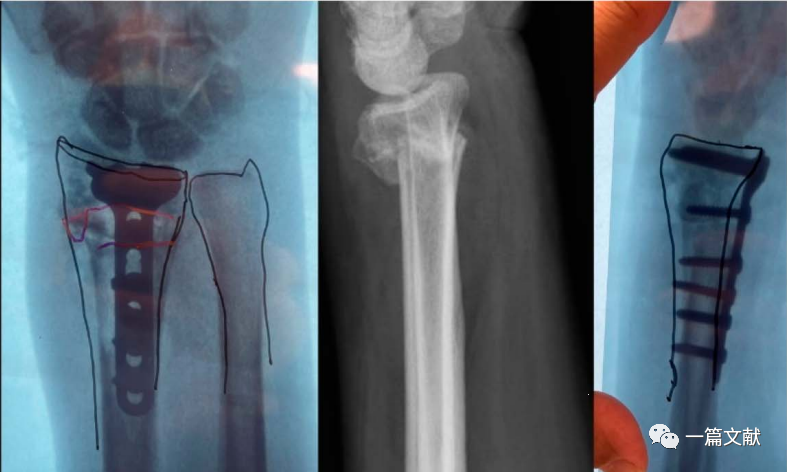

4、骨折畸形愈合的截骨矫形手术

此法可极大的简化截骨矫形手术过程,如下图:

最后为该患者矫形术后的下肢全长位片,患肢力线恢复满意